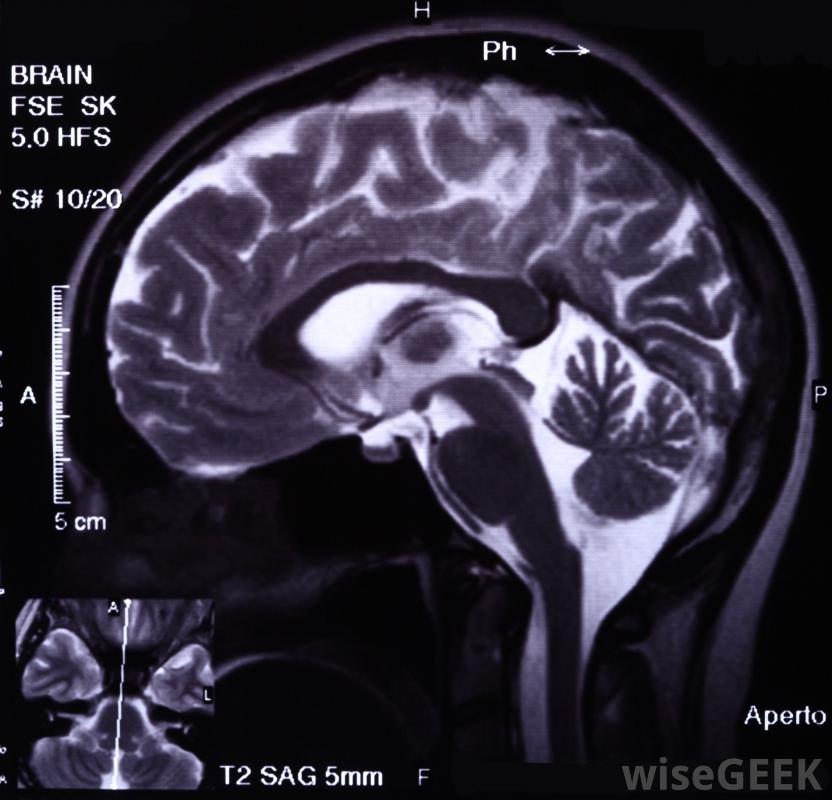

难治性癫痫是一种抵抗药物治疗的癫痫发作性疾病。临床医生和研究人员对如何定义难治性癫痫存在一些争论。因此,这个术语有多种用法,当患者的癫痫被描述为难治性、耐药或无反应时,建议询问更多关于诊断的详细信息,这将有助于患者理解护理人员得出的结论。医生可以使用脑电图来确认癫痫的诊断癫痫发作在普通人群中并不少见。人们可能只经历一次发作,再也不会发作,尤其是在儿童早期。在其他人中,癫痫发作发展成癫痫,一种有多种形式的疾病。癫痫是根据患者发作的类型来分类的,也可以根据治疗效果来分类。对药物没有反应的病人可能是癫痫手术的候选者。在一些病人中,尽管尝试了几种抗癫痫药物,癫痫仍会持续,病人被称为难治性癫痫。当病人在一段时间内经历一次发作复发时,一些临床医生会做出这种诊断其他人可能会诊断难治性癫痫患者,如果在服药和停药时没有明显的差异。如果患者在服药期间出现较少的癫痫发作,患者将不会被视为无反应者,因为他或她实际上对药物有反应,尽管不完全CT扫描可用于调查患者的病因;难治性癫痫患者有可能开始对药物产生反应并有所改善。相反,药物治疗效果好的患者可能会复发并发展为难治性癫痫。癫痫患者的治疗因不遵守药物治疗方案而变得复杂。不按指示服药的患者可能会出现癫痫发作,如果患者对不遵医嘱不诚实,医生可能会认为患者患有难治性癫痫。癫痫根据患者经历的癫痫发作类型进行分类,也可以根据其对治疗的反应程度进行分类癫痫发作早、发育迟缓、神经系统检查异常、癫痫丛集以及在治疗开始前多次发作的人患难治性癫痫的风险增加对药物治疗无反应的癫痫患者可以选择生酮饮食、癫痫手术,或迷走神经刺激。一旦发现患者对多种抗癫痫药物无反应,这些治疗方法可能成为可能的选择。通常这类患者会去癫痫门诊,接受癫痫专科医生的治疗,该专家可以提供最新的研究和治疗方案患有难治性癫痫的人可能需要因突发性癫痫发作而进行紧急医疗。癫痫是根据一个人经历的癫痫发作次数和对治疗的反应程度来分类的。难治性癫痫对药物治疗有抵抗力大多数癫痫发作是由大脑的电异常引起的。